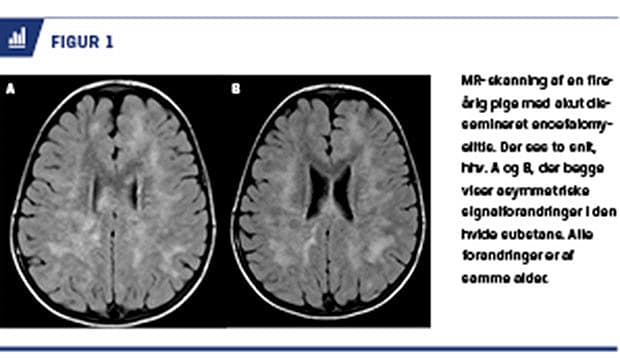

ADEM er karakteriseret ved akut opstået polyfokal CNS-udfaldssymptomer, inklusive encefalopati. Dette ses på MR-skanning ved multifokale læsioner, typisk af samme alder, mest udtalt i hvid substans (Figur 1).

ADEM er oftest en monofasisk sygdom, men tilbagevendende og multifasiske sygdomsforløb er beskrevet.